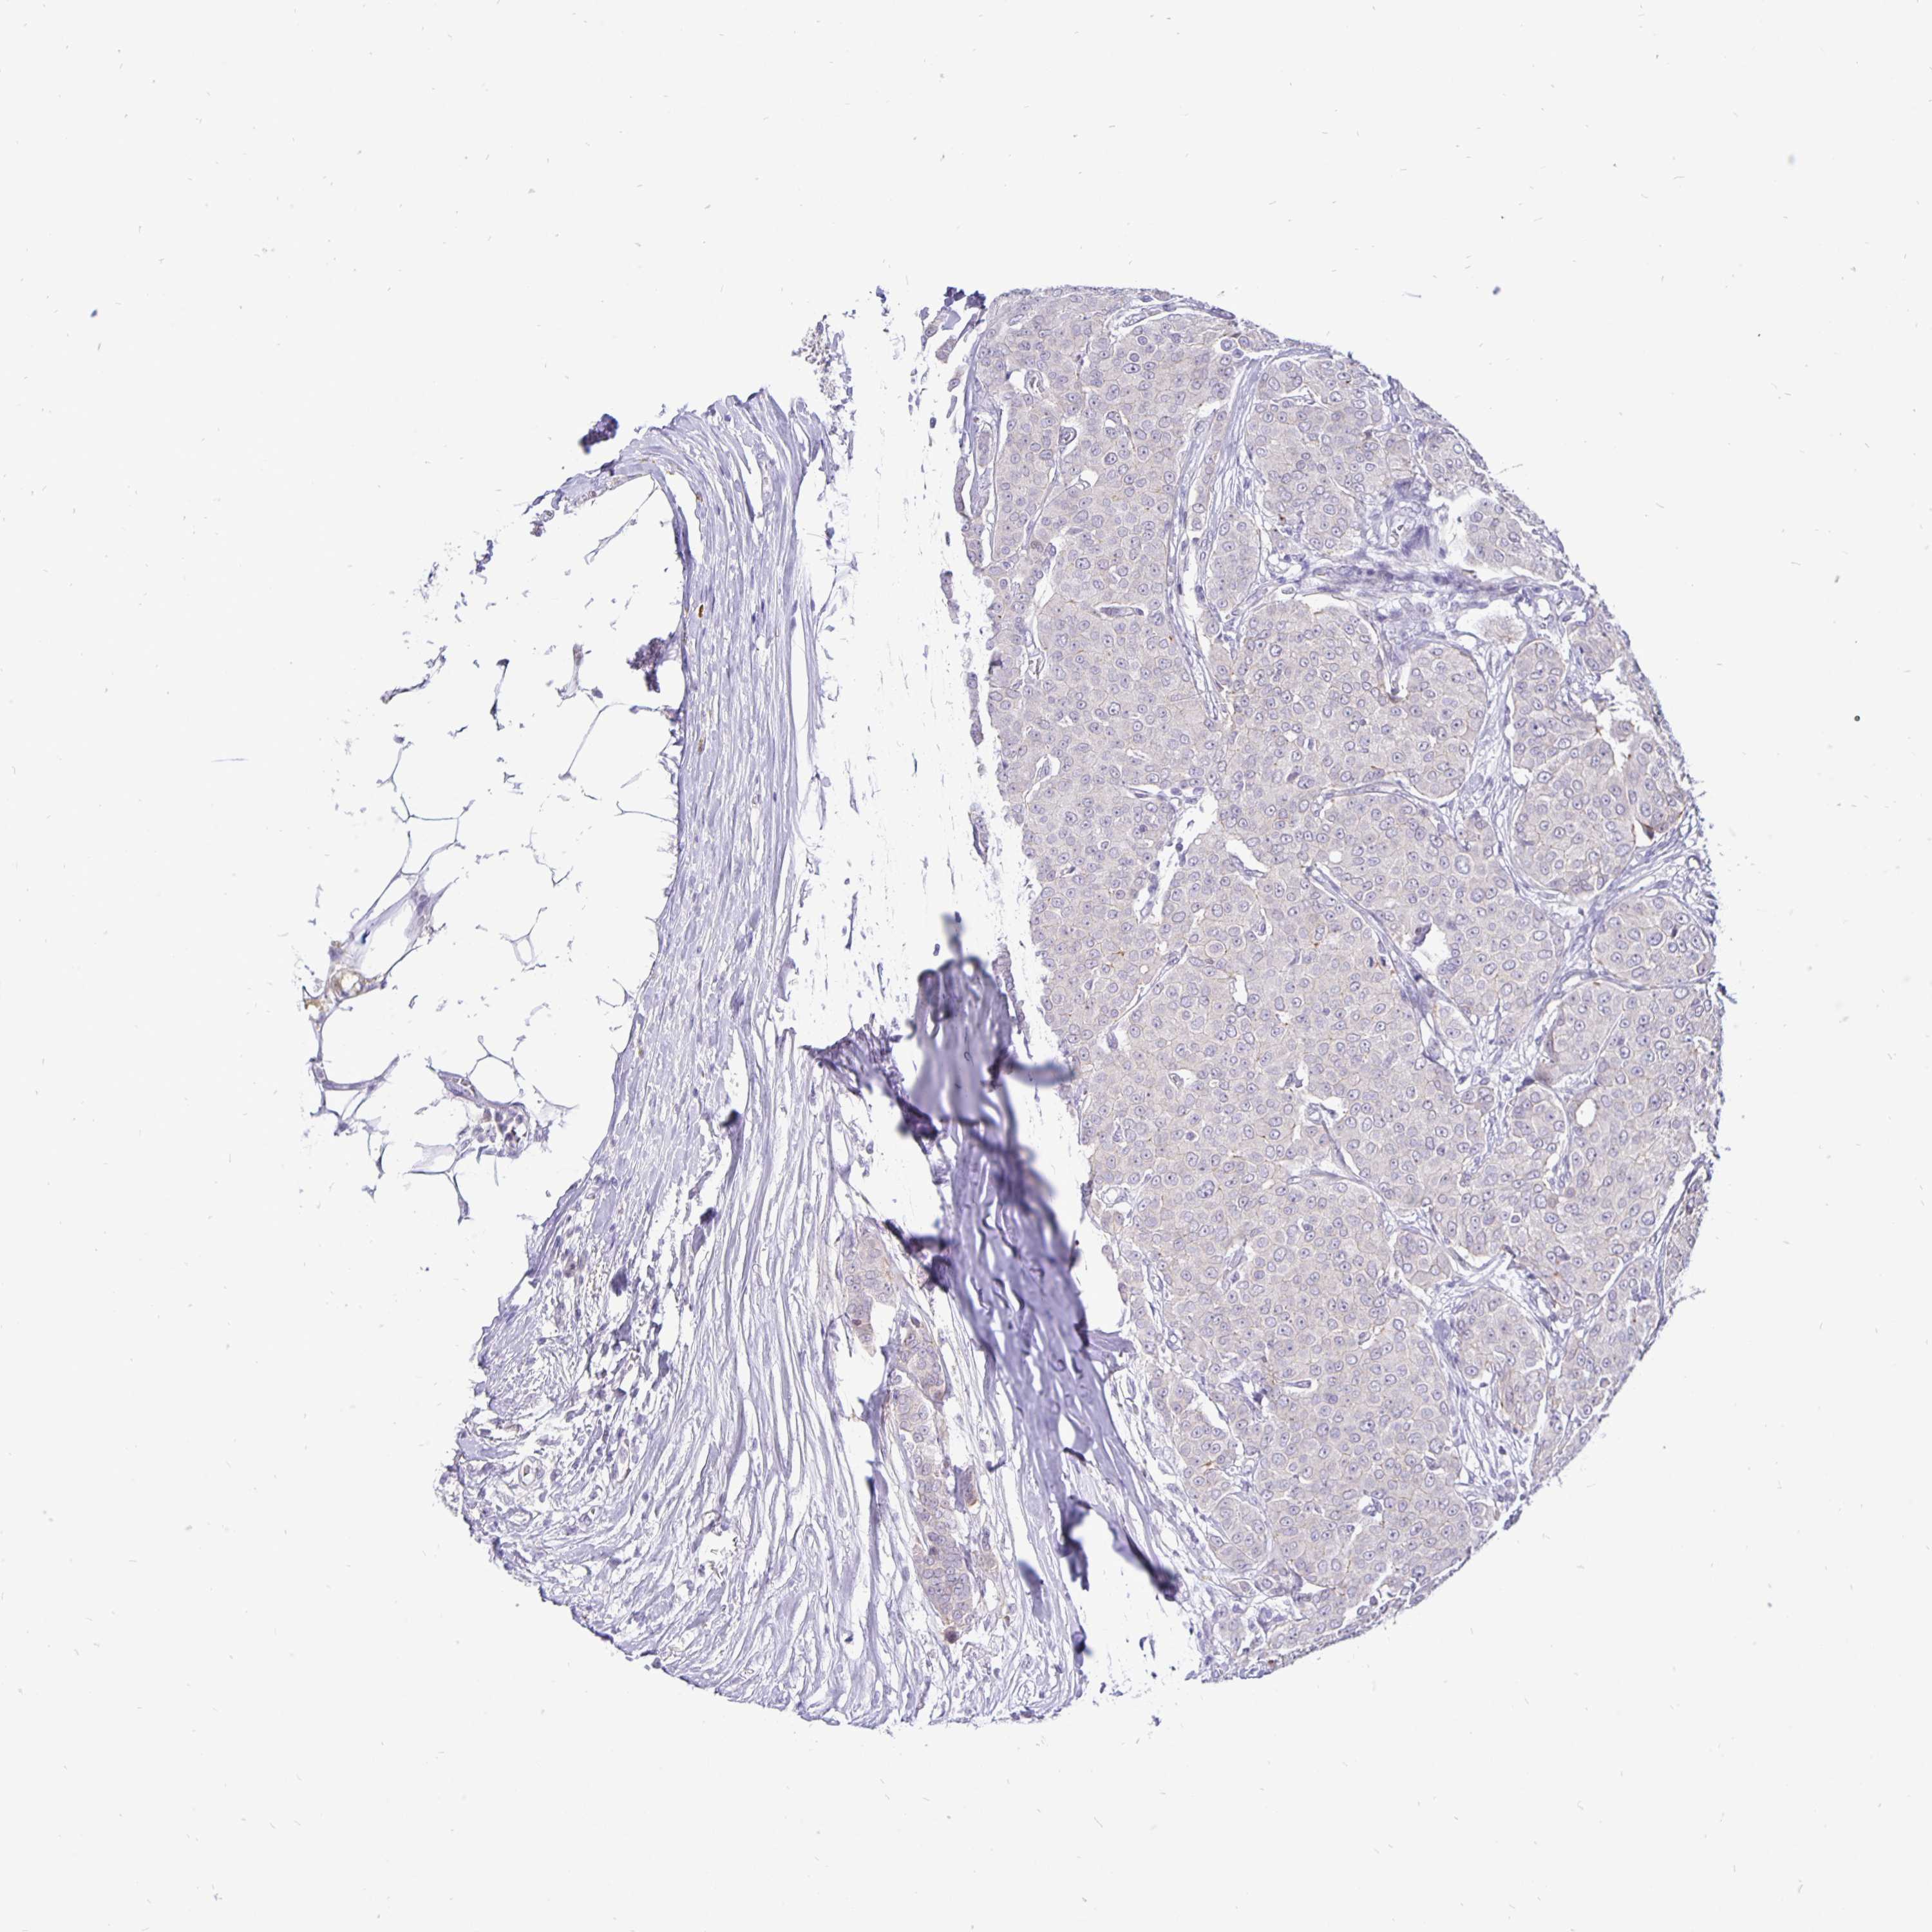

BRCA TCGA BRCA VALIDATION PROTEIN EXPRESSION

ANTIBODIES

AND

VALIDATION